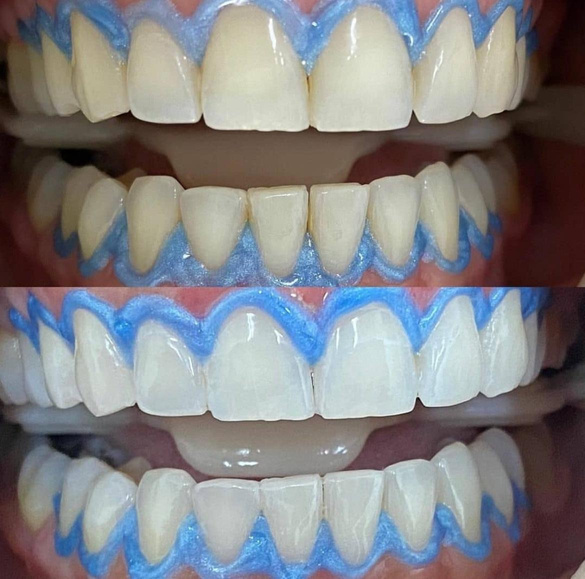

resina composta em dente anterior

curso de restaurações estéticas em resina composta

realidade clínica: resina composta